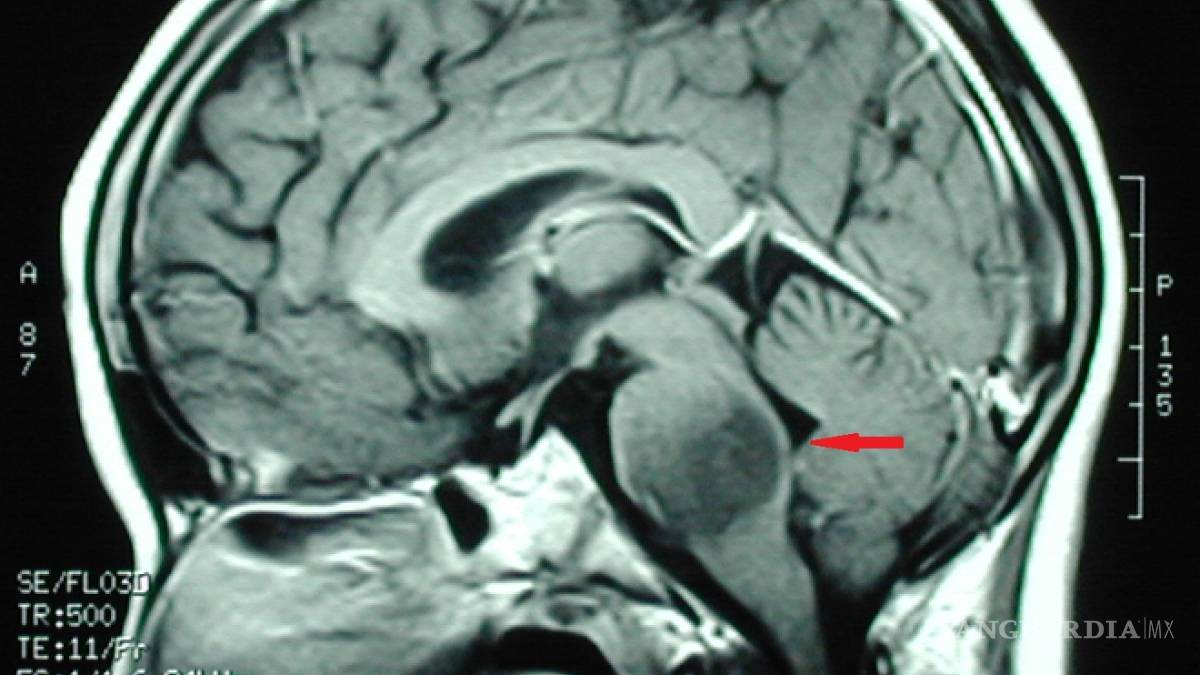

Los especialistas dieron a conocer que el tratamiento se basa en utilizar una mezcla de medicamentos que, en cierta secuencia, causan un efecto positivo en el tratamiento de los gliomas de tallo cerebral

Quienes padecen de esa enfermedad presentan un tumor que se llega a calificar como inoperable, sin embargo, los médicos de Monterrey, con una experiencia de 20 años trabajando de la mano, desarrollaron un procedimiento denominado quimioterapia intraarterial superselectiva, la cual ha dado una esperanza de vida a sus pacientes de todo el mundo.

En entrevista, los especialistas dieron a conocer que el tratamiento se basa en utilizar una mezcla de medicamentos que, en cierta secuencia, causan un efecto positivo en el tratamiento de los gliomas de tallo cerebral o incluso de otros tumores cerebrales.

Luego, explicaron, se hacen estudios de imagen para monitorear el avance que presentan los pacientes y en caso de no encontrarse actividad tumoral, se suspende el tratamiento y continúa en observación el paciente.